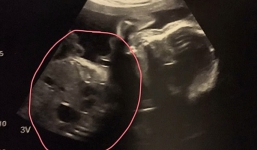

Mẹ bầu mắc hội chứng lạ, ốm nghén suốt 9 tháng từng nghĩ đến chuyện bỏ con

08-09-2017 | 10:16